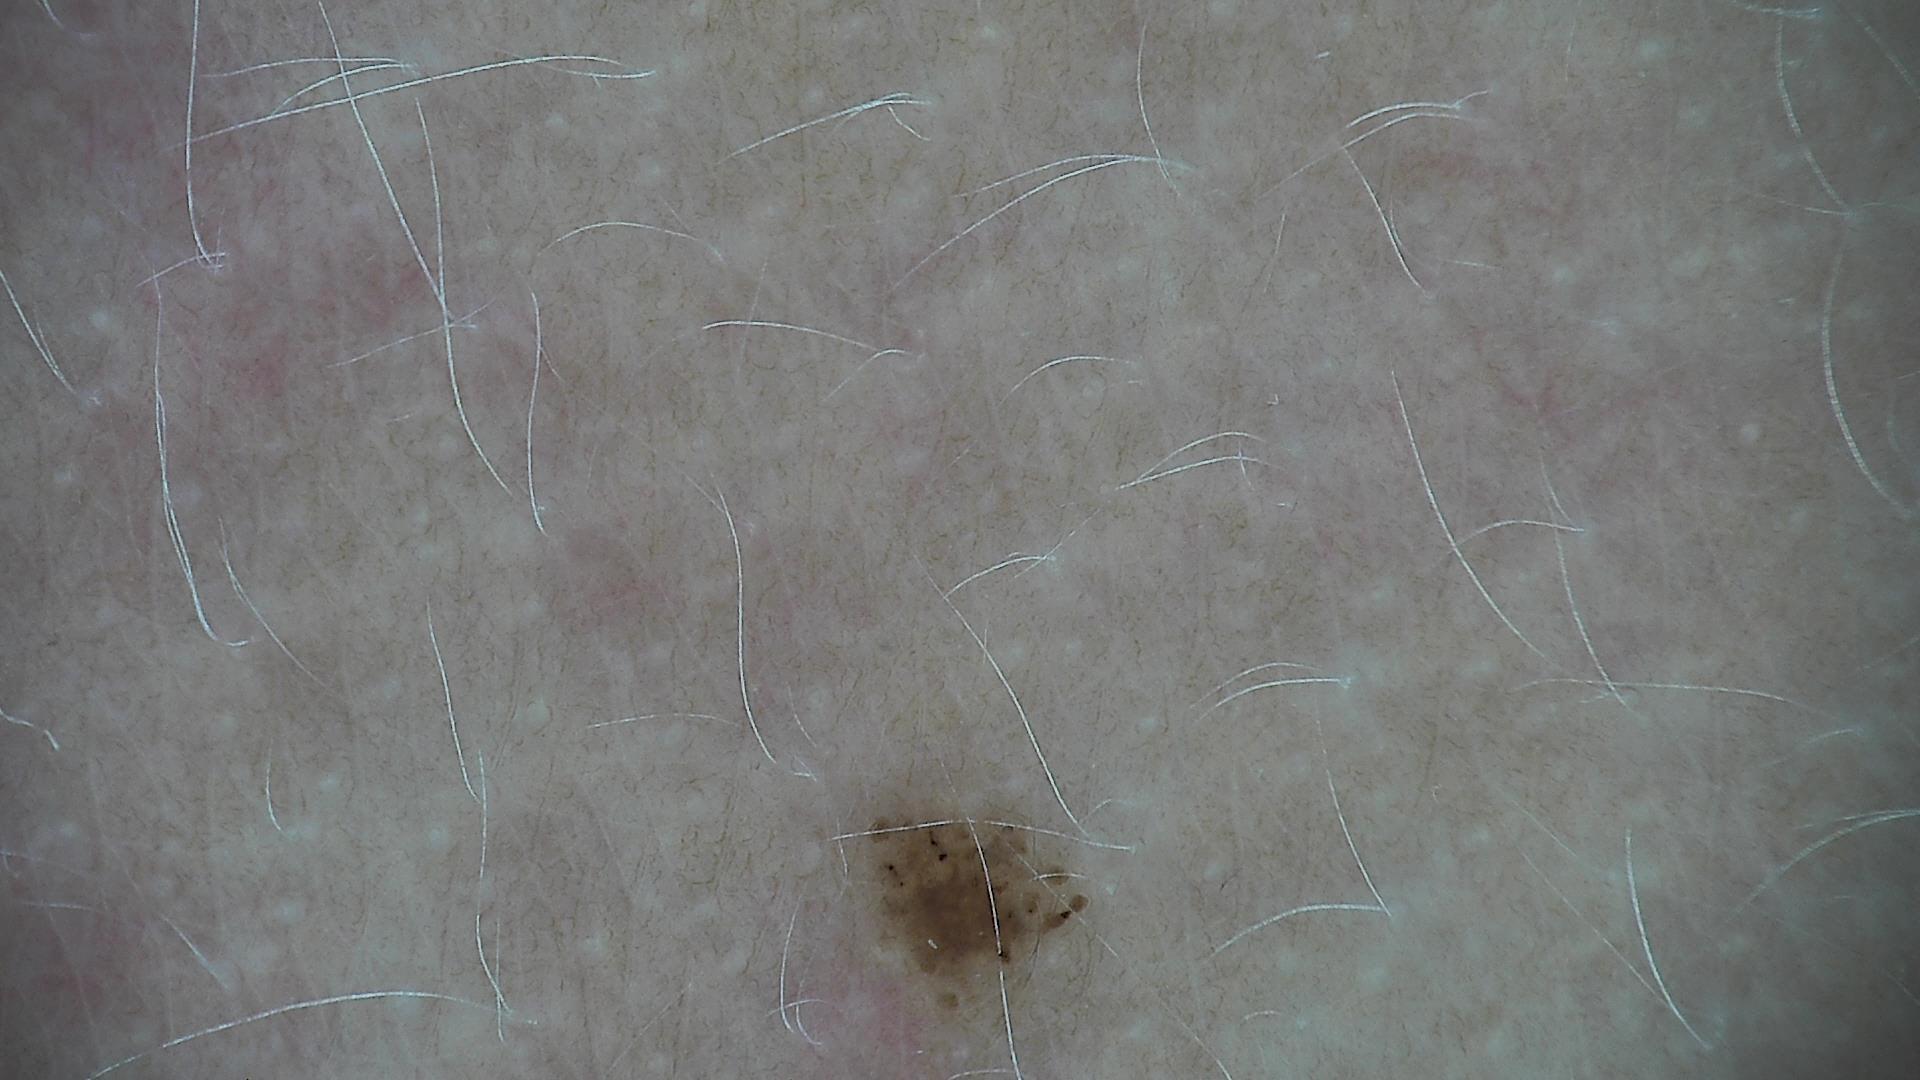

ISIC_1152373

diagnosis_1

Benign

diagnosis_2

Benign melanocytic proliferations

diagnosis_3

Nevus

diagnosis_4

Nevus, NOS, Junctional

image_type

dermoscopic

melanocytic

True